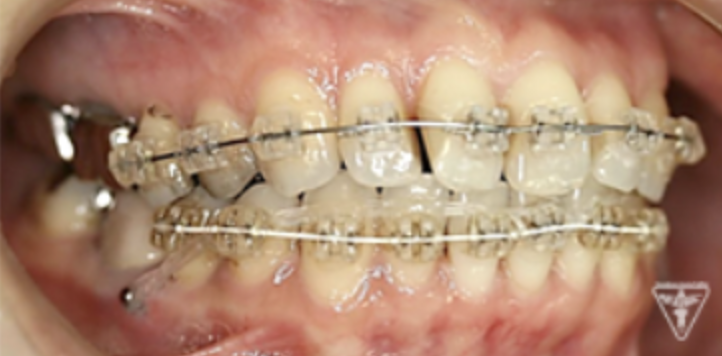

矯正治療

矯正治療による歯軸、叢生改善